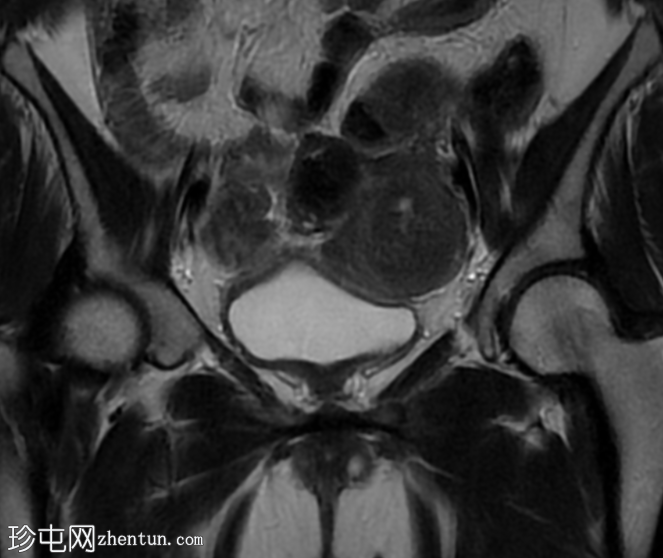

冠状位

STIR序列

2.jpeg

双角子宫,有两个子宫角和一个宫颈(单颈双角子宫)

右角正常,分区解剖结构正常,无肌层病变

左角局灶性前壁腺肌症,前壁交界区边界不清,肌层内可见多个高信号灶

两个小的间质性肌瘤和一个大的浆膜下肌瘤

宫颈纳博氏囊肿

该病例表现为双角子宫单宫颈(双角单颈子宫),左侧单侧局灶性子宫角腺肌症,以及多发性子宫肌瘤。